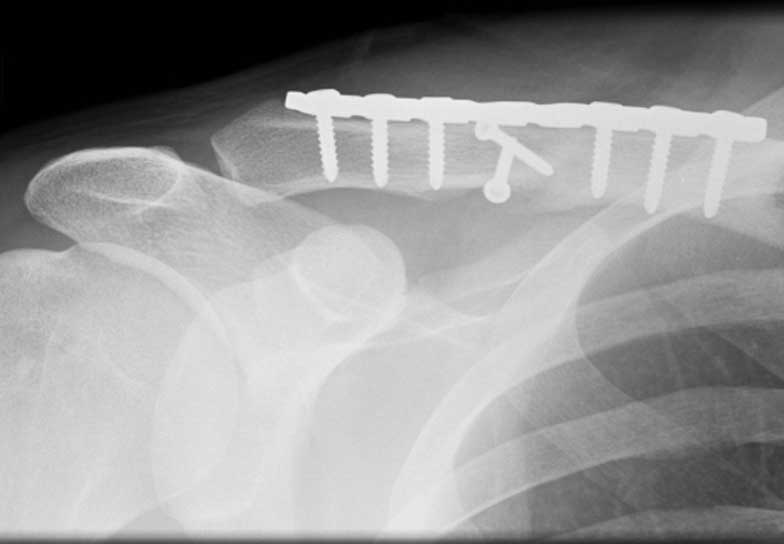

In my practice and what is generally becoming more accepted in the literature, is that most fractures of the clavicle that are displaced, angulated or overlapped are best treated with an operation. This operation can either be performed by realigning the bones in their original shape using a plate and screws on top of the bone or by using a pin that goes down the centre of the bone. Both of these techniques are successful and the decision generally comes down to the fracture pattern and the preference of the surgeon. The idea of the operation is to make the patient as comfortable as possible by making the fracture stable, and therefore allowing the patient to return to normal activities as soon as possible.

Generally all displaced fractures of the distal clavicle require surgery to increase the incidence of union. In my practice, the operation is performed by realigning the bones back to their original position using a plate and screws on top of the bone. The advantage of fixing them with a plate and screws generally means that you can start to move the arm a lot quicker and to also decrease the incidence of non-union.

The operation is performed with the patient under a general anaesthetic, in other words, completely asleep, and a small 3-4 cm incision is made under the collarbone, at the end of the shoulder. The fractured bone ends are exposed and put back into position using a plate and screws as shown below.

This fixation also needs reinforcement using special sutures around the plate and around the bone next to the clavicle called the coracoid process. The sutures are used to decrease the deforming forces from your shoulder muscles. In the majority of cases, in my hands, the operation is extremely successful resulting in the bone healing and the return of near normal function. In a small number of cases, the plate needs to be removed if it irritates the patient under the skin.